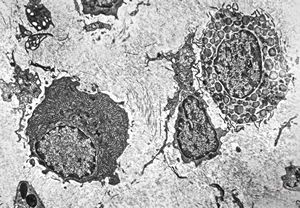

M,62y. | plasmocytoma - nasal cavity